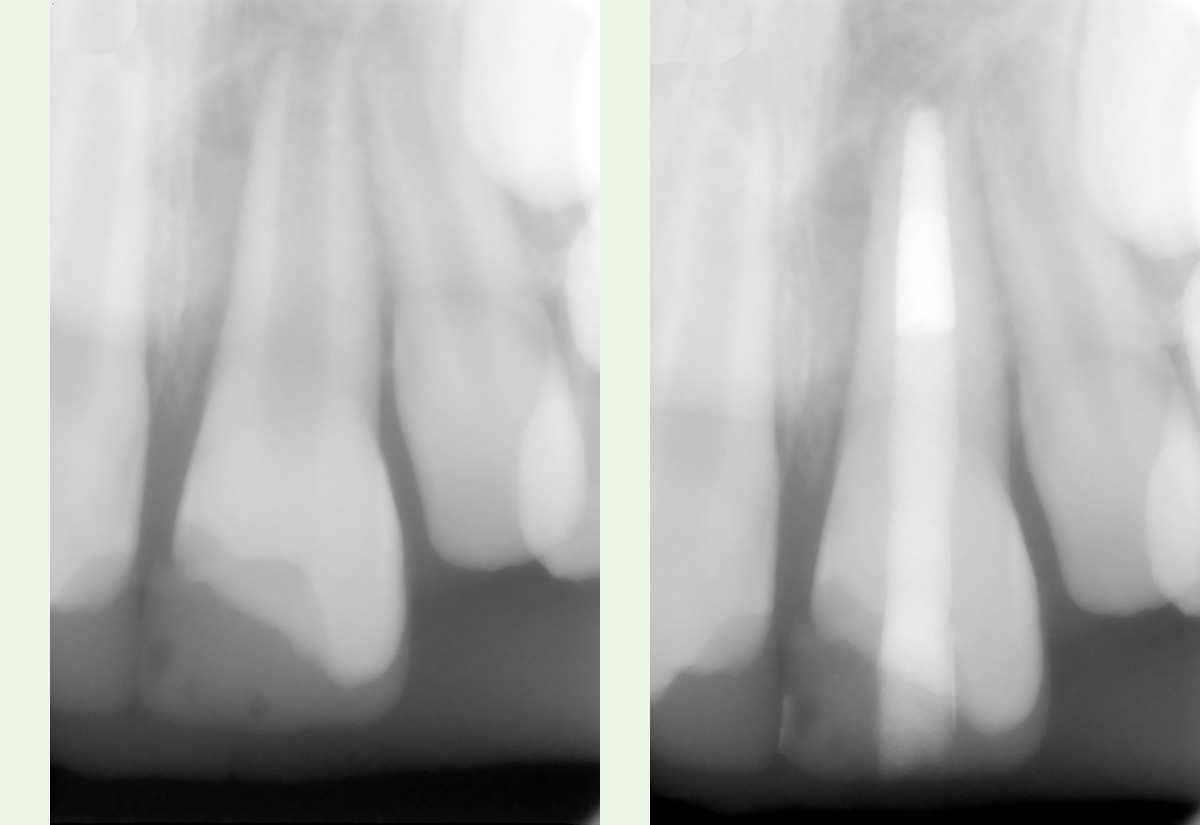

Rettung eines Unfallzahnes II

2. Die Zahnpulpa (der „Nerv“) des Scheidezahnes überlebte den Unfall nicht und Bakterien drangen in den Zahn ein. Trotz der verspäteten Behandlung konnte der Zahn gereinigt und verschlossen werden.

3. Nach knapp 2 Jahren hat sich der Knochen an der Wurzelspitze regeneriert und der Zahn ist ohne ästhetische Beeinträchtigung in Funktion.